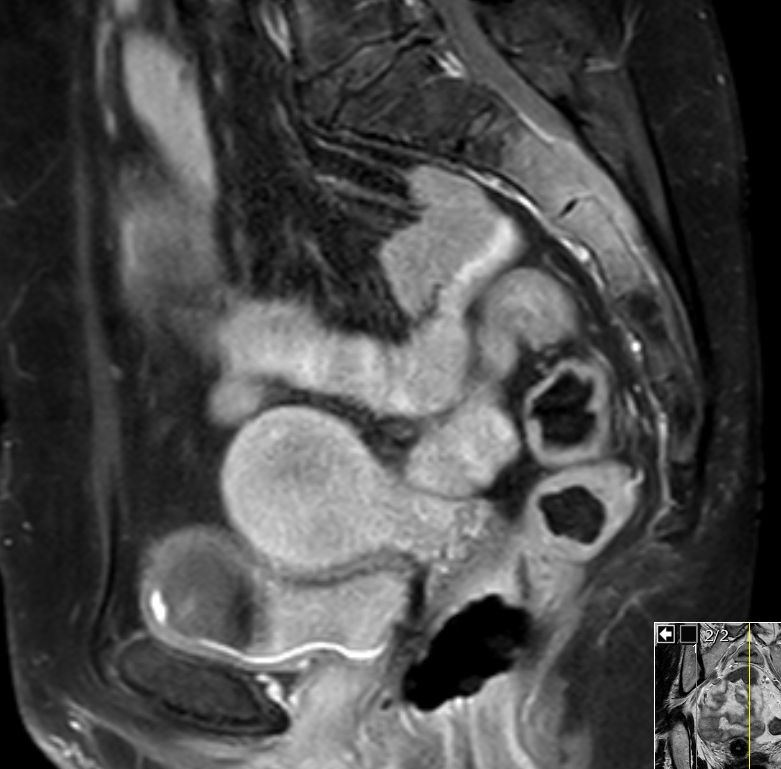

| Kreuzbein | 51jährige Bürokauffrau in leicht reduziertem AZ. KI 80. Sie hat starke Schmerzen in der Kreuzbeinregion, so dass sie nicht auf dem Rücken liegen kann. Ferner besteht eine Blasenentleerungsstörung. Das MRT zeigt eine tumoröse Infiltration des 2. und 3. Kreuzbeinsegmentes. Der Tumor ist in den Spinalkanal eingebrochen und hat die Nerven der Cauda aequina eingehüllt. ![]() |